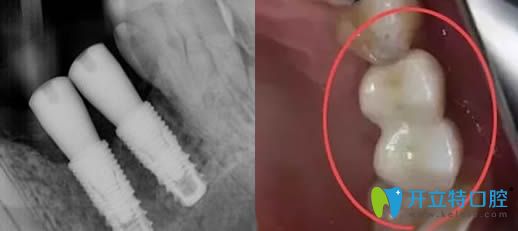

從片子中看種植體種歪斜的原因有多種,包括按牙骨情況設(shè)計的,也有技術(shù)失誤造成的......

種植體種歪了的效果圖片

所以種植體歪了大家也不要過分擔(dān)心,并不全是種植失敗了。但如果歪斜較重,只能重新種植了,?因為傾斜角度過大,則會造成承受咀嚼的側(cè)向力過大,從而造成種植失敗的。

因此,對于輕微傾斜的植體,在安裝牙冠時,醫(yī)生會通過角度基臺來調(diào)整角度,這樣后期牙冠是整齊的,但植體的歪斜是不可逆的。

種植體歪了可以做牙冠調(diào)整修復(fù)